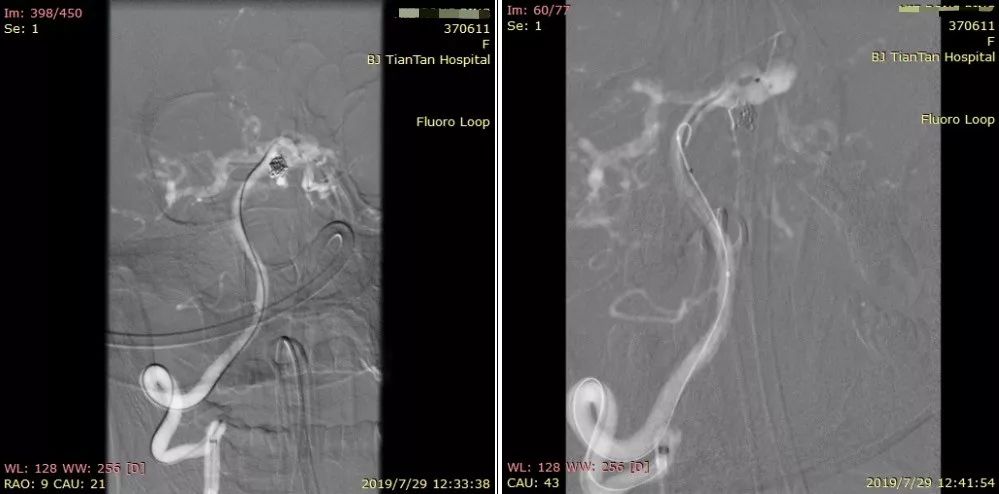

Select Plus支架微导管及Echelon 10微导管顺利到位 (图4)。

图4

经动脉瘤内预置的微导管送入第二枚弹簧圈时,弹簧圈有向载瘤动脉脱出倾向,决定释放支架(4.0 mm * 23 mm Enterprise支架) (图5) 。

图5

4.0 mm*23 mm Enterprise支架释放完毕(图6)。

图6